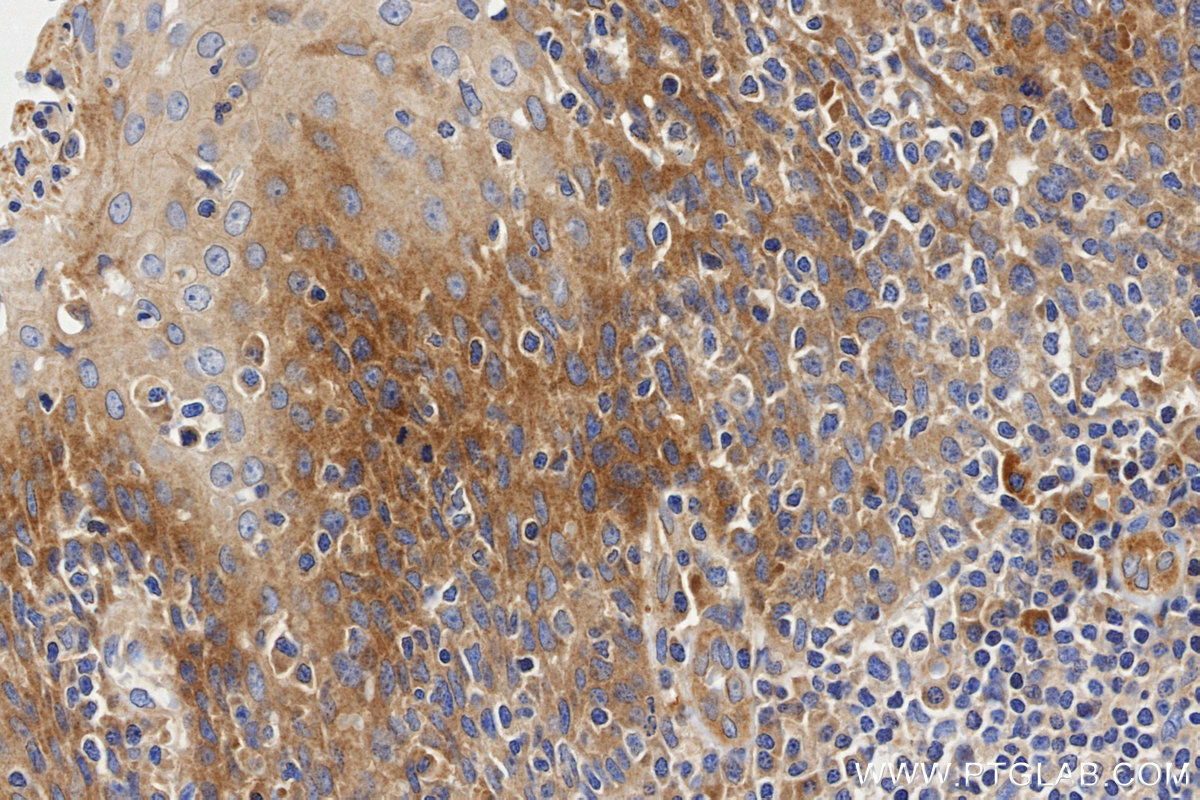

| Positive IHC detected in | Human Tonsil tissue Note: suggested antigen retrieval with TE buffer pH 9.0; (*) Alternatively, antigen retrieval may be performed with citrate buffer pH 6.0 |

| Immunohistochemistry (IHC) | IHC : 1:500-1:2000 |